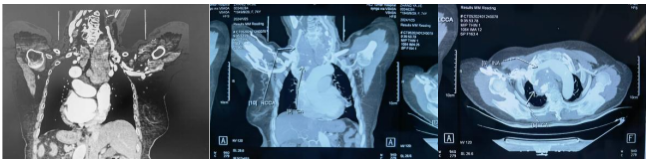

74岁的张大娘多年前出现心脏难受、喘气费劲、身上无力等症状,最近一段时间,她呼吸困难,连进食都无法完成,身体迅速衰弱。前期检查发现,张大娘的胸部心包上存在一个巨大的肿瘤。全家人抱着最后一丝希望来到哈医大肿瘤医院寻求帮助。

患者由于肿瘤长期压迫心包和肺动、静脉,已经出现心包积液,并伴有严重的房颤、三尖瓣重度反流、肺炎。哈医大肿瘤医院头颈外科鼻咽喉口腔二病房项丞教授经过专业判断,发现肿瘤的来源是甲状腺,虽然颈部的包块并不明显,但肿瘤向下生长,从颈部一直长到胸部,成为了“压在心里的大石头”。

据哈医大肿瘤医院头颈外科鼻咽喉口腔二病房主任裴荣介绍,哈医大肿瘤医院在治疗颈胸交界处的肿瘤有独到的优势。此次项丞教授团队在未开胸骨的情况下,将体积大、位置低的心包上肿瘤从颈部完整取出,大大降低了患者的手术创伤和并发症,充分体现了哈医大肿瘤医院头颈外科治疗技术优势。(吕元景)